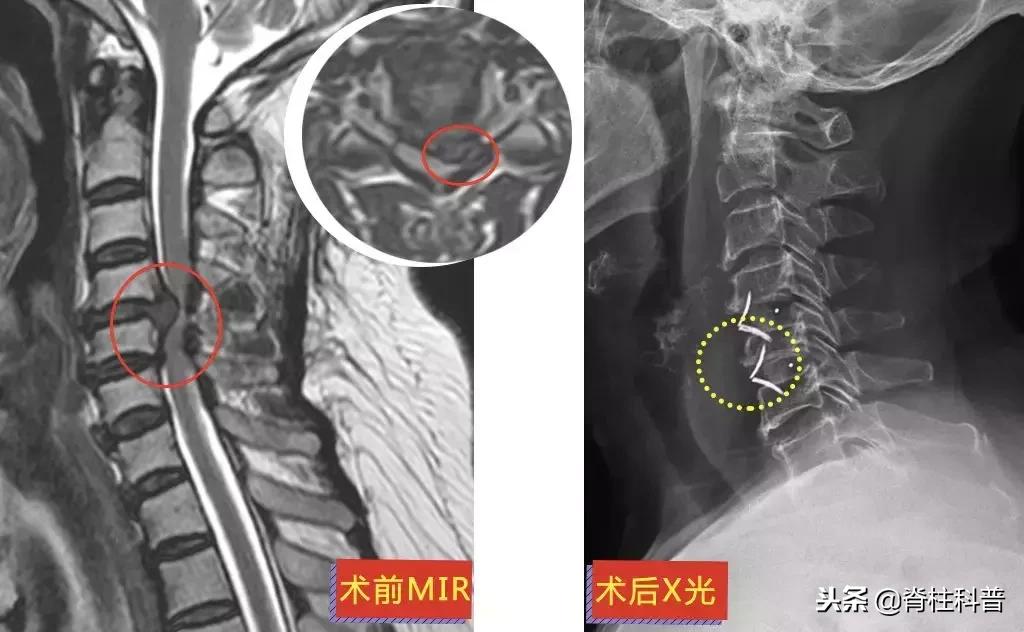

10天后,再次予以颈椎牵引治疗,症状稍缓解,可是颈痛发作频繁。经过熟人介绍,特意从茂名来到广州南方医科大学第三附属医院,找到张忠民主任医师治疗。在2018年9月20日在门诊被主任以“神经根型颈椎病”收治入院。10月3日手术,术后疼痛症状得到明显改善。

▲ 李三姨:术前MRI与术后X光